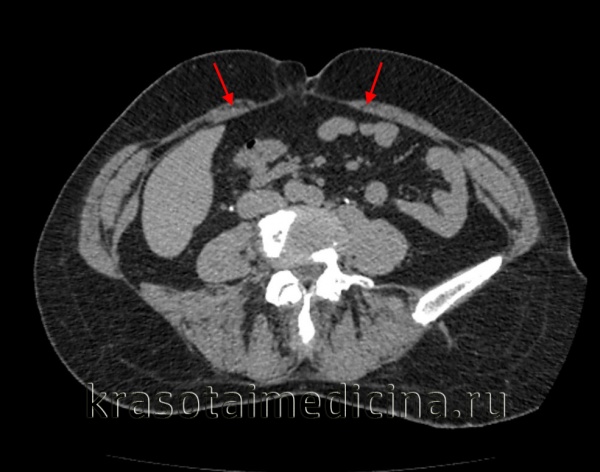

КТ ОБП. Расхождение прямых мышц живота (красные стрелки) у пожилой женщины.